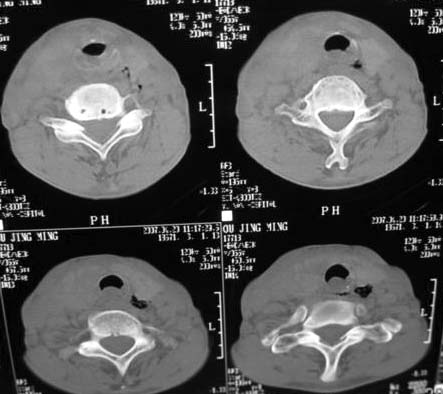

以下是引用dyqct在2007-4-20 16:19:00的发言:[br]考虑:1、左侧梨状窝区破裂伴左颈深、浅部气肿。[br] 2、右侧甲状腺区血肿(请追问病史是否伤及右颈部)。[br] 3、建议病情稳定后增强扫描除外右侧甲状腺腺瘤。